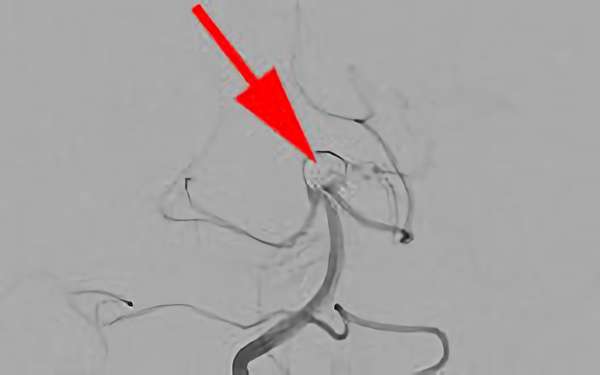

'26年4月

左内頚動脈脳動脈瘤

No.1630 手術前